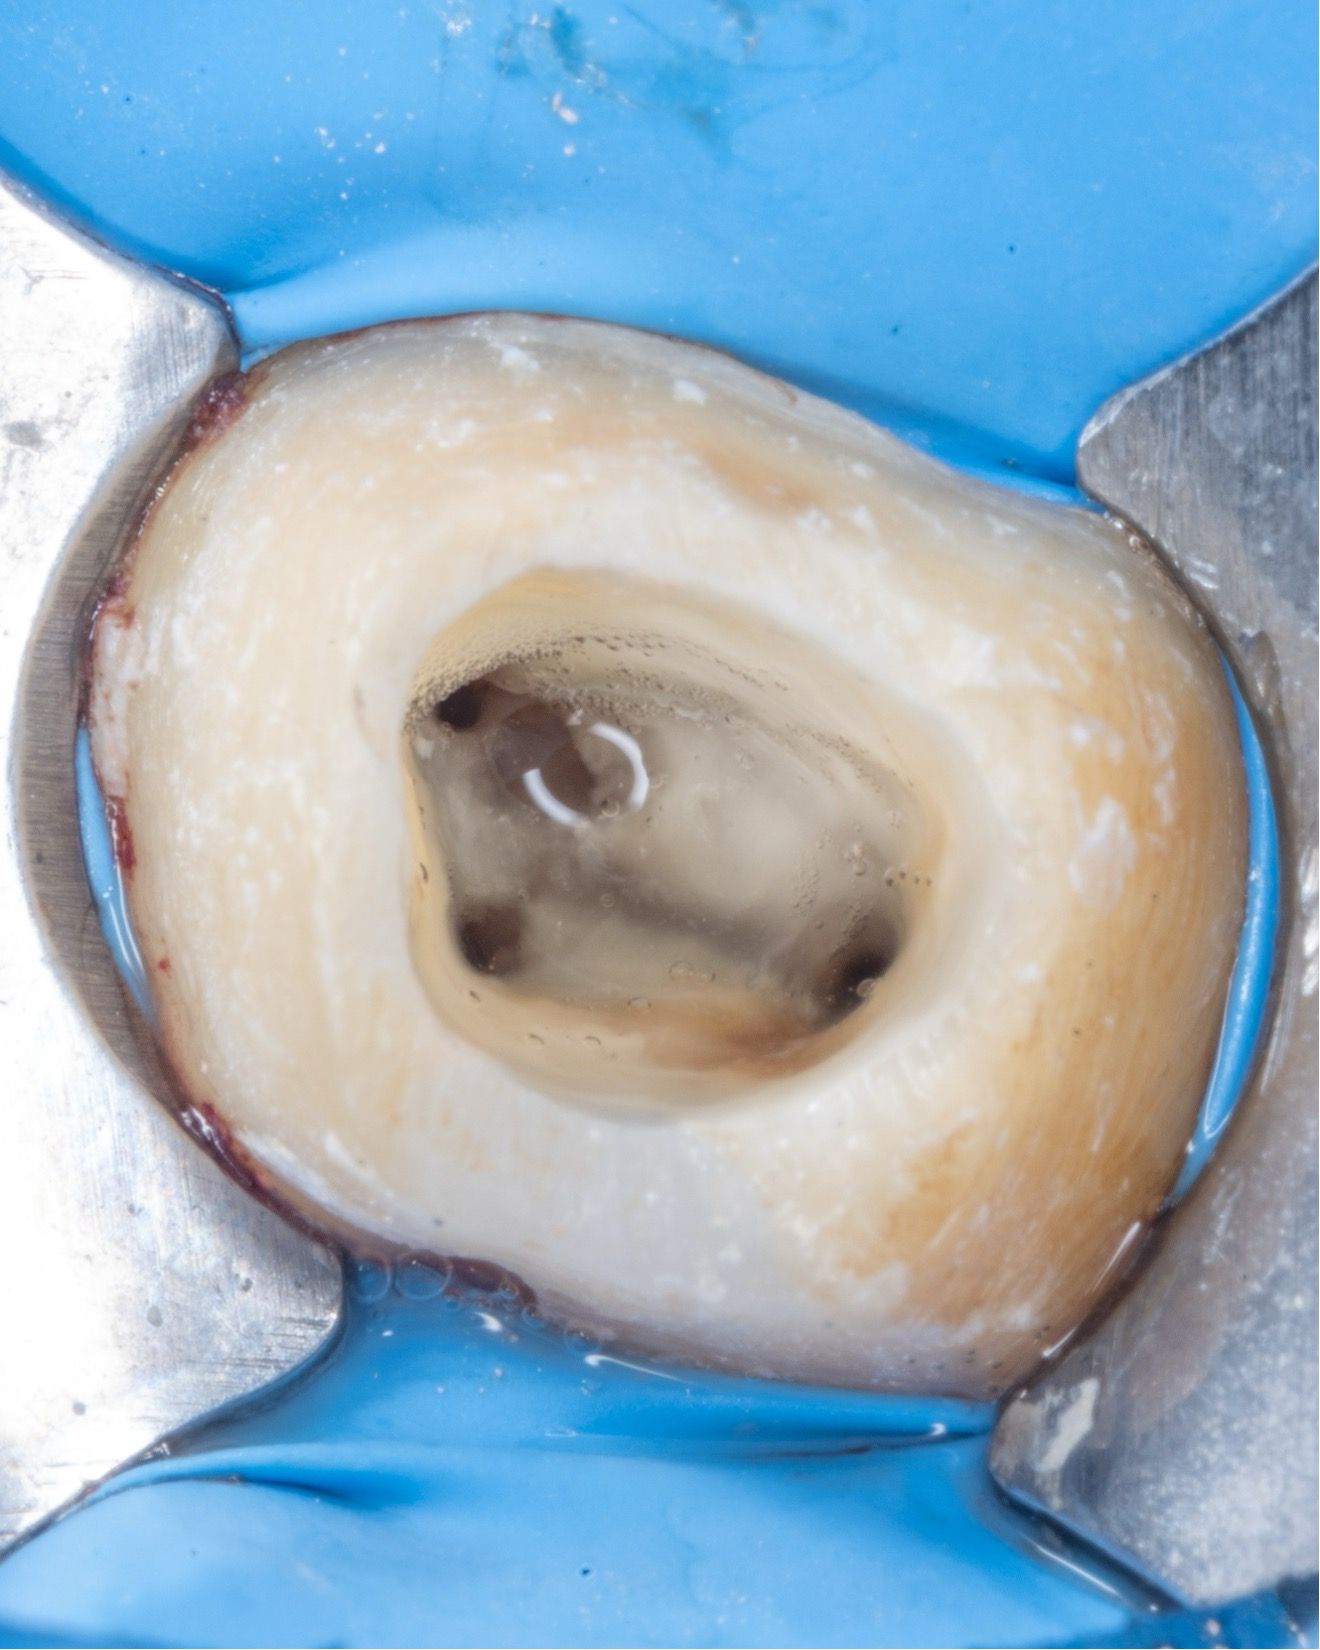

ilk seansta koronal restorasyon kaldırıldı ve kanal dolgu materyali retreatmant eğesi(Perfect, retreat one) ile uzaklaştırıldı. Dental operasyon mikroskobu altında meziobukkal 2. kanal arandı ancak koronal kısımda meziobukkal kanal ile birleştiği görüldü (Şekil 5).

(Şekil 5). Kavite görüntüsü

Apikal üçlüdeki alet ED 87 numaralı ultrasonik uç ile enerji verilerek çıkartıldı. Basamak atlanarak radyografik olarak doğrulandı. (Şekil 6a-6b)